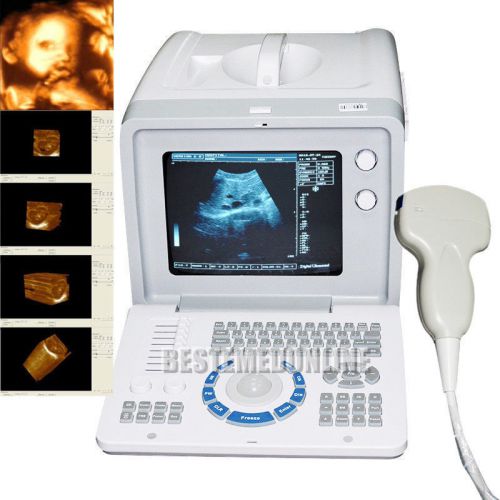

3D PC Plateform Based Full Digital Portable Ultrasound Scanner+3.5mhz convex pro

3D PC FULL digital Portable ultrasound scanner machine 3.5mhz Convex 3Y WARRANTY

Internal 3D 3.5mhz convex+6.5mh Transvaginal Portable Ultrasound Scanner machine

Internal 3D 3.5mhz convex probe Portable Ultrasound Scanner machine warranty

FDA Portable Digital Ultrasound Scanner CONVEX PROBE 3D software optional linear

CE FDA Full Digital Portable Ultrasound Scanner+Transvaginal Probe +3D Software

Portable Ultrasound Scanner Sysytem Machine +7.5MHZ Linear probe+WARRANTY

CE FDA Ultrasound Scanner Machine +Convex Probe +Free 3D Software + 2ys warranty